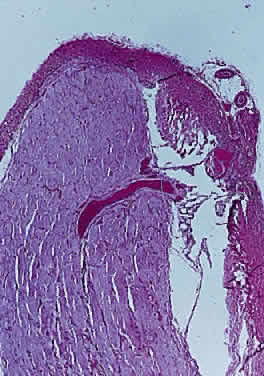

Intraoperatively, hemangioblastoma appears as a reddish, circumscribed tumor that typically is well demarcated from the nerve, although often the central portion is involved. Microscopically, the most striking feature is the abundance of vascular channels, most of which have the appearance of capillaries. Reticulin-staining highlights the vascular network. Between them are stromal cells containing abundant vacuolated cytoplasm, which is due to the presence of lipid. Although bland, the nuclei of the stromal cells are variable in appearance and may exhibit focal marked hyperchromasia (Figs. 46 and 47). Electron microscopy shows that the large stromal cells contain intracytoplasmic particles of lipid and glycogen. Scattered foci of extramedullary hematopoiesis may be present as a consequence of erythropoietin production by the tumor cells. Mast cells also are often readily identifiable. Small cysts are frequent, and the cyst wall consists of gliosis, in which may be found numerous Rosenthal fibers.

Fig. 46. Hemangioblastoma of optic nerve. Multiple capillary vessels are separated by foamy cells (hematoxylin and eosin staining).

Fig. 47. Hemangioblastoma of optic nerve. Foamy cells are a prominent feature between the thin-walled capillary vessels (hematoxylin and eosin staining).